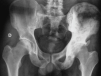

Fig. 2. Hueso ilíaco izquierdo con imágenes osteoblásticas características de enfermedad de Paget.